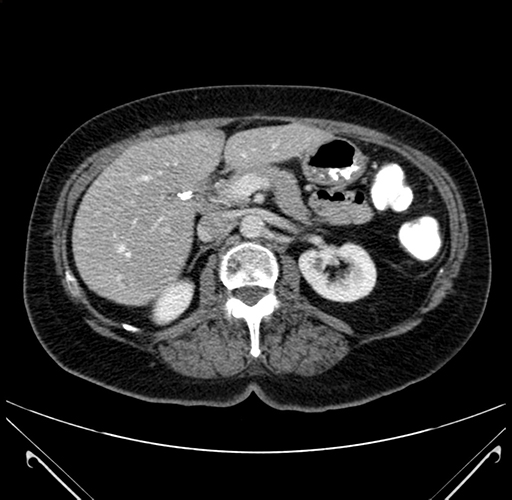

Axial Venous